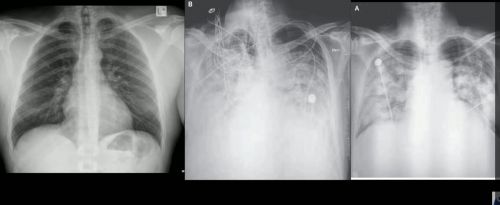

까맣게 보이는 정상인의 폐 CT와 달리 신종 코로나바이러스 감염증 환자의 폐는 하얗게 변했습니다.

[박동원/한양대병원 호흡기내과 교수 : 전반적으로 간유리 음영이 관찰되고 있습니다. 폐 전반에 염증이 심하다는 것을 의미할 수 있습니다.]

위쪽이 배 쪽 아래쪽이 등 쪽인데 시간이 지날수록 등 쪽의 허파 부위는 더 하얗게 변했습니다.

[박동원/한양대병원 호흡기내과 교수 : 아래쪽에 좀 더 음영이 진한 것으로 보아서 바이러스 폐렴이 좀 심각하게 진행하고 있고 호흡 부전 증후군으로 진행되고 있는 것은 아닌가 생각됩니다.]

걸리면 CT로 찍었을 때 폐가 점점 하얗게 변하는데 저 하얀 게 모두 가래, 고름이 쌓여서 저렇게 된 거다.